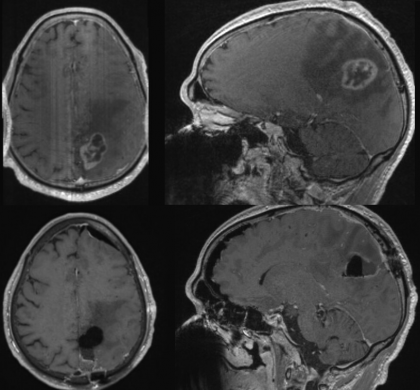

foto: RMN arătând un glioblastom pre- și post-operator. Credit: Dominique Higgins, MD, PhD